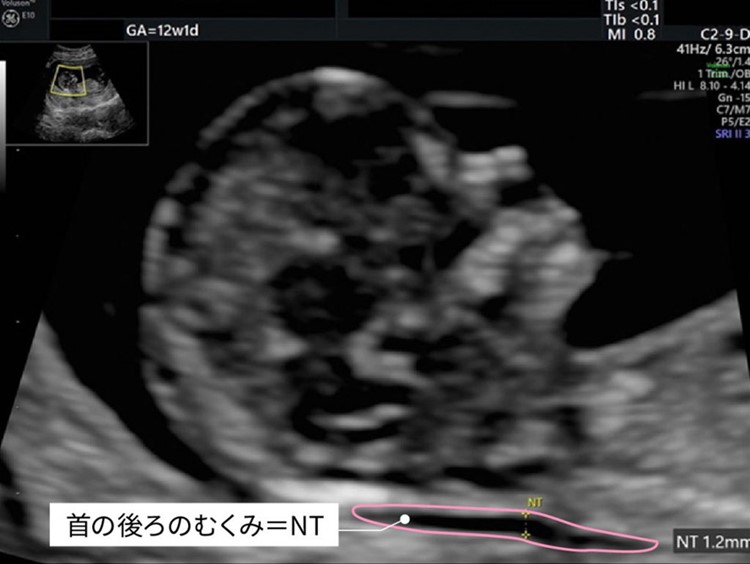

また、赤ちゃんのNT(首の後ろのむくみ)などの超音波項目から(条件が揃えば)、21/18/13トリソミー、妊娠高血圧腎症や胎児発育不全、早産についても確率を出すことができます。